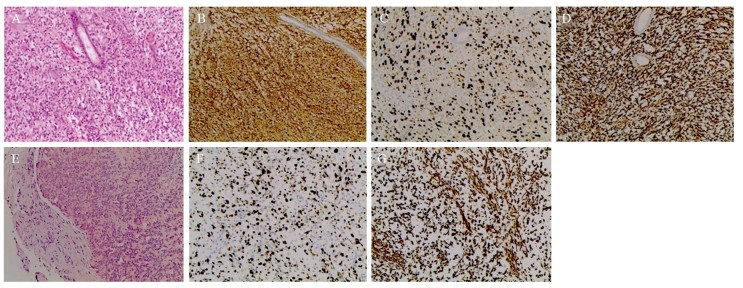

患者,男,5岁,右肾后肾腺肉瘤术后1年,因左小腿近段疼痛1月,于2017年8月17日收入我院骨科。入院前1月患儿出现左侧小腿近段疼痛,1周前加重并出现跛行,行患肢X线检查,发现胫骨近端占位,遂入院治疗。既往患者因“右肾占位”于2016年8月16日于我院泌尿外科行右肾根治性切除术,见图 1。病理:瘤细胞形态一致,呈管状、腺泡状排列。间质呈无细胞的水肿样、黏液样或者玻璃样变的状态,免疫组织化学结果:CK(-)、Vim(+)、CD34(-)、CD99(+)、WT1(-)、Ki-67(阳性细胞数40%)、S100(-)、Des(-)、EMA(-)、Act(-)、Myo(-),后肾腺肉瘤,见图 2。术后患者未行后续治疗。入院查体:左小腿近端压痛,明显肿胀,胫骨结节水平周径较对侧增粗2 cm,膝关节屈伸活动正常。全身骨扫描示:右股骨上段可见异常核素浓聚,相应部位髓腔内见片状低密度及高密度影,左胫骨上段可见异常核素浓聚,相应部位骨皮质破坏伴周围软组织包块形成,见图 3A。膝关节及胫腓骨CT示左侧胫骨近中段骨质破坏。MRI示:胫腓骨近中段见不规则T1稍高信号,T2高信号影,胫骨近段骨皮质不连续,周围软组织内可见不规则T1稍高信号,T2高信号影,见图 3B、F。胸腹部CT未见局部复发及肺、肝等内脏转移征象。患者入院后为明确病变性质及来源,于2017年8月23日行左胫骨病变切取活检术,术中刮取髓腔病变呈“鱼肉样”肿瘤组织送检。病理示:破碎灰白质韧组织一堆,直径1 cm。区域瘤细胞小圆形,在幼稚的黏液间质中弥漫性分布,部分呈梭形;无病理性核分裂相;无坏死。免疫组织化学检测示:CK(-),WT1(-),Vim(+),Ki-67(阳性细胞数50%),Desmin(-),SMA(+/-),CD34(血管+),S100(-)。少许间叶源性恶性肿瘤,对比既往右肾肿瘤病理,符合后肾腺肉瘤骨转移,见图 2。于2017年9月起给予AI方案(ADM 60 mg/m2+IFO 8 g/m2,21天为一疗程)化疗3周期,其中第2周期化疗结束出现Ⅳ度粒细胞缺乏伴粒细胞缺乏性发热,经G-CSF、预防应用抗生素后体温及白细胞数量逐渐恢复正常,第3周期化疗给予减量25%后仍再次出现Ⅳ度骨髓抑制、粒细胞缺乏。化疗结束后查体显示左小腿肿胀较化疗前明显减轻,胫骨结节水平周径较对侧增粗0.5 cm。复查胫腓骨X线示病变较前好转,MRI提示软组织包块明显缩小,髓腔内病灶未见明显变化,见图 3C、G。对侧股骨近端转移灶未见明显变化。因患者家属拒绝继续化疗,2018年1月起改用甲磺酸阿帕替尼每日250 mg维持,并继续每3月随访,病情持续控制稳定。至2018年9月患儿突发右侧大腿近端肿胀、疼痛,复查发现右股骨近端髓腔内异常信号,伴股骨干周围异常信号,左侧胫骨近端病变较前无明显变化,见图 3D、H,骨扫描提示右股骨核素浓聚范围较前增大,左胫骨近端核素浓聚较前无明显变化。考虑病情较前进展,病情评估PD,患儿家属拒绝进一步化疗,遂于2018年9月后每4周加用一次唑来膦酸1 mg静滴,患儿耐受性良好,无发热等不良反应,肝肾功能无异常,至2018年12月末次复查MRI见左侧胫骨近端病变无明显变化、右侧股骨近端髓腔内病变无变化、股骨干周围异常信号消失。查体右侧大腿近端肿胀较前明显消退,周径与对侧大腿同水平相等。病情评估PR,患者未出现异常反应,末次随访MRI显示左侧胫骨近端转移灶及对侧股骨近端转移灶未见明显变化,见图 3E、I、R,目前患者病情变化仍在进一步随访中。

后肾肿瘤是罕见的肾脏原发肿瘤,其中以MA相对常见,该肿瘤最早由Brisigotti[4]于1992年命名。目前尚未见大宗病例分析。MA可发生于任何年龄,多见于成人,女性多见,男女比例约为1:2[3]。MA起源于肾皮质小管,多数学者认为其是一种具有良性生物学行为的罕见肿瘤,但随着报道数量的不断增多,在一些病例中MA表现出了侵袭性和转移性[4-5],因此其生物学特性尚有待探讨。Li等[6]通过对18例病理学诊断为MA的患者进行回顾性分析,发现MA具有三种组织学亚型,分别为典型后肾腺瘤、恶性后肾腺瘤和不同恶性成分共存的后肾腺瘤,认为MA是一种具有不同生物学特性的异质性肿瘤。MA患者在就诊时多无明显临床症状,多为体检时发现,有些患者可出现血尿或红细胞增多症[3]。该病治疗方式以手术切除为主,对于瘤体较小的后肾腺瘤,可选择保留肾单位的肿瘤切除术,单纯的后肾腺瘤多预后良好,术后无复发和转移征象[6-9]。Xie等[10]的报道中,因为在后肾腺瘤中发现了肉瘤成分,因而称之为后肾腺肉瘤,该肿瘤恶性程度高,预后极差,免疫组织化学指标显示其患者肿瘤的上皮成分中AE1/AE3、CD57、EMA、CK7、CD117均为阳性,间质成分中Vim、CD10为阳性,但是WT1在间质成分中则显示为弱阳性。Picken等[2]报道的患者免疫组织化学则显示其上皮成分中除AE1/AE3为阳性外其他上皮标志物表达均阴性,而Vim、CD34、CD117间质成分则表达为阳性。本例患者骨病灶标本镜下组织形态呈明显间叶源性细胞其Vim、SMA,CD34均呈现强阳性或中等阳性表达,结合免疫组织化学结果,符合原发病灶中的肉瘤成分转移而来的判断。